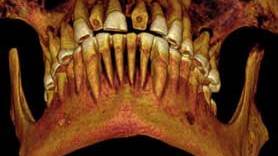

The man, whose name is unknown, was in his 20s or early 30s, and his teeth were in horrible shape. He had "numerous" abscesses and cavities, conditions that appear to have resulted, at some point, in a sinus infection, something potentially deadly, the study researchers said.

Nevertheless the ancient specialist tried something to relieve his suffering. Using a piece of linen, perhaps dipped in a medicine such as fig juice or cedar oil, the expert created a form of "packing" in the young man’s biggest and perhaps most painful cavity, located on the left side of his jaw between the first and second molars.